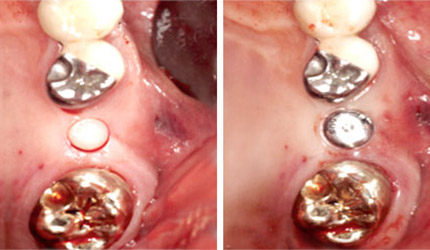

УСТАНОВКА БЕЗ РАЗРЕЗОВ

Тело имплантата Anyridge имеет диаметр 3,3 мм,

поэтому достаточно сделать небольшое отверстие

в десне и можно установить имплантат без разрезов

и швов. При этом сразу устанавливается

формирователь десны, поэтому после приживления

имплантата можно сразу снимать слепки

и изготавливать коронку.

УСТАНОВКА СРАЗУ ПОСЛЕ УДАЛЕНИЯ ЗУБА

Благодаря выступающим виткам резьбы можно

достичь очень высокой стабильности в лунке

удаленного зуба. Поэтому имплантат Anyridge

идеально подходит для установки сразу после

удаления зуба. Это позволяет снизить

количество операций до одной, а также сохранить

максимум костной ткани и десны.